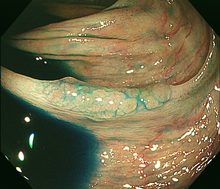

2)内視鏡的粘膜切除術(EMR)

大腸にできた小さな腫瘍やポリープが平坦または陥凹した形の場合、ポリープにスネアが掛かりにくいため、粘膜下に生理食塩水などを注入して隆起させ切除します。切除する病変の大きさや形状によりますが、1日から数日間の入院が必要です。